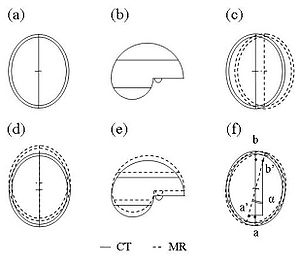

Comparison between Magnetic Resonance Imaging Estimates of Extracranial Cerebrospinal Fluid Volume and Physical Measurements in Healthy Dogs

Publication: Vet Radiol Ultrasound. 2015 Nov;56(6):658-65. PMID: 26311617 Authors: Reinitz LZ, Bajzik G, Garamvölgyi R, Petneházy Ö, Lassó A, Abonyi-Tóth Z, Lőrincz B, Sótonyi P. Institution: Faculty of Veterinary Science, Department of Anatomy and Histology, Szent István University, Godollo, Hungary. Background/Purpose: Dosages for myelography procedures in dogs are based on a hypothetical proportional relationship between bodyweight and cerebrospinal fluid (CSF) volume. Anecdotal radiographic evidence and recent studies have challenged the existence of such a defined relationship in dogs. The objectives of this prospective cross-sectional study were to describe CSF volumes using magnetic resonance imaging (MRI) in a group of clinically healthy dogs, measure the accuracy of MRI CSF volumes, and compare MRI CSF volumes with dog physical measurements. A sampling perfection with application optimized contrast using different flip-angle evolution MRI examination of the central nervous system was carried out on 12 healthy, male mongrel dogs, aged between 3 and 5 years with a bodyweight range of 7.5-35.0 kg. The images were processed with image analysis freeware (3D Slicer) in order to calculate the volume of extracranial CSF. Cylindrical phantoms of known volume were included in scans and used to calculate accuracy of MRI volume estimates. The accuracy of MRI volume estimates was 99.8%. Extracranial compartment CSF volumes ranged from 20.21 to 44.06 ml. Overall volume of the extracranial CSF increased linearly with bodyweight, but the proportional volume (ml/bodyweight kilograms) of the extracranial CSF was inversely proportional to bodyweight. Relative ratios of volumes in the cervical, thoracic, and lumbosacral regions were constant. Findings indicated that the current standard method of using body weight to calculate dosages of myelographic contrast agents in dogs may need to be revised. |